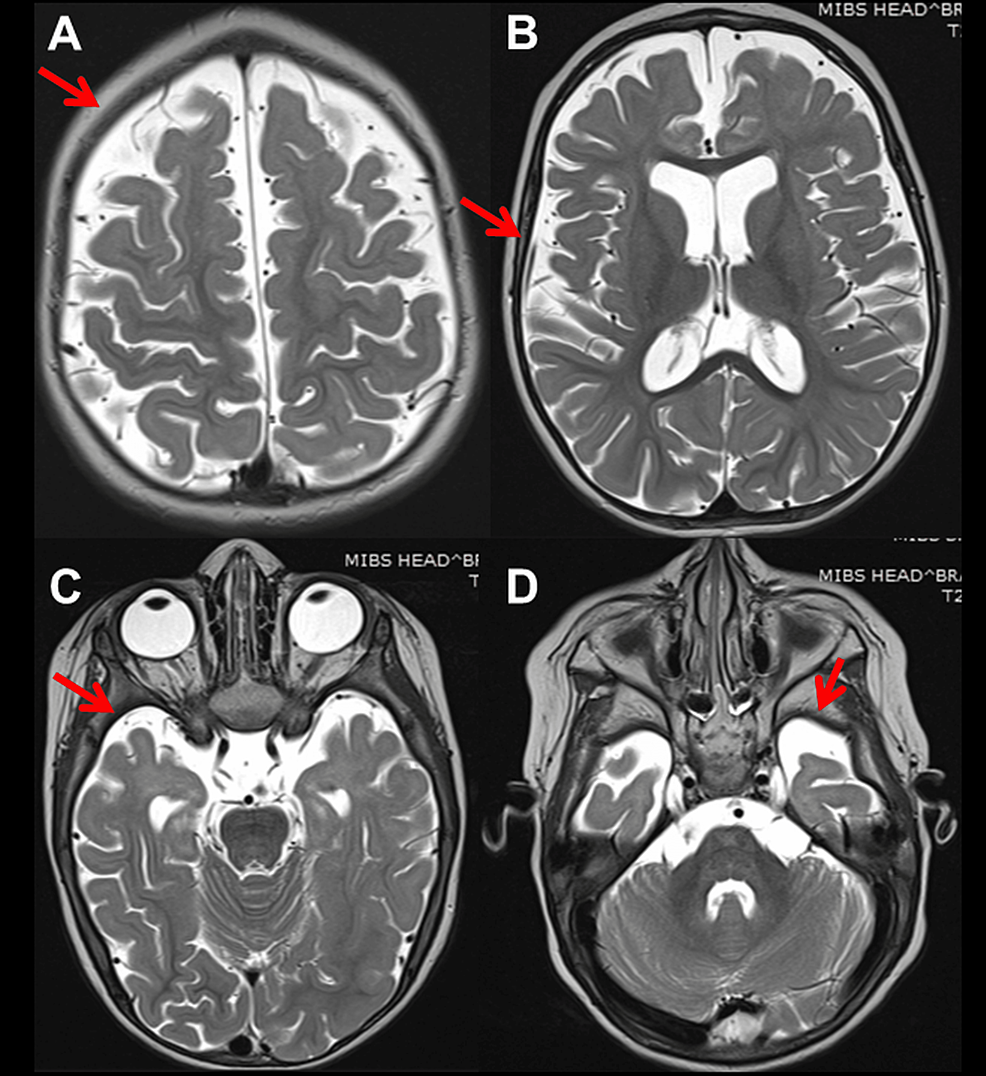

A key test for identifying multiple sclerosis during diagnosis, or to confirm a relapse, is magnetic resonance imaging MRI. Being encased in a magnetic tube that, when operational, sends out diazepam 10 mg for mri noise and requires complete stillness can be intimidating. Even a claustrophobic person me! By now, MRI technicians in radiology labs have acquired the appropriate headgear to protect your ears and help you block out the noise. Most also come equipped with piped-in music you can concentrate on to relax.